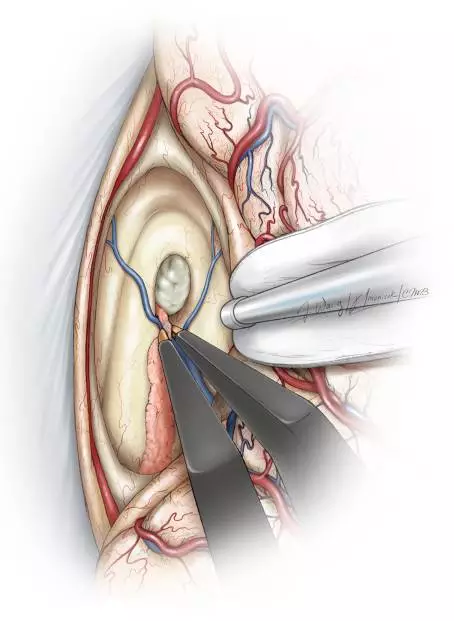

图7. 图示脉络丛、透明隔静脉和丘纹静脉的手术解剖。通过脉络膜裂前部一小段分离扩大室间孔的关键操作是在隔静脉汇入丘纹静脉之前切断。穹隆和丘纹静脉必须被保留。尽管笔者更愿意沿丘脑侧分离脉络裂而不是沿穹隆一侧分离来达到保护穹隆的目的,但是脉络裂的实际解剖更可能提示最合理的分离界面。换句话来讲,笔者并不推荐固定的分离策略(总是沿着丘脑脉络带或者穹隆带)。穹隆构成室间孔前壁的边界,在器械移动过程中应该注意保护。

图10. 将覆盖在Monro孔和静脉角表面的脉络丛前方切断,然后轻柔的钝性分离和电凝。肿瘤通常会扩大室间孔,但是无法提供足以完整切除肿瘤的手术通道(Redrawn from Tew,van Loveren, Keller*)。

图11. 将隔静脉在临近室间孔处汇入丘纹静脉时分离并电凝,然后切断(上图)。下图提供了关于右侧脑室及相关解剖的术中照片。